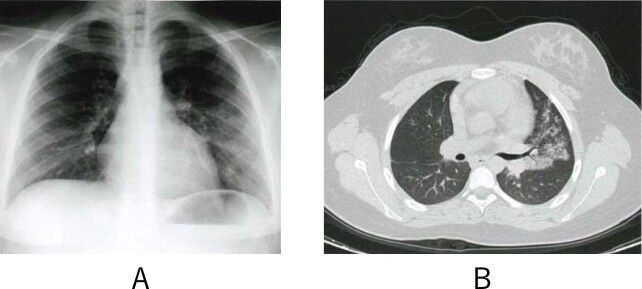

2 ステロイド 免疫抑制剤併用による間質性肺炎治療中 間質性肺炎の悪化と血中サイトメガロ ウイルスアンチゲネミア B Dグルカンの上昇を認めた48歳の女性 サイトメガロウイルス肺炎とニューモシスティス肺炎の合併 検査と技術 40巻10号 医書 Jp